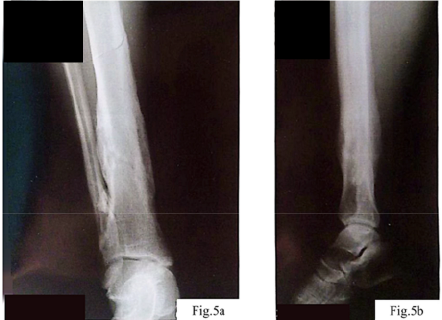

Clinical case. The patient, a 40-year-old man, sustained an injury to the right tibia as a result of tripping over a tree stump while carrying firewood. His medical history included a cervical spine injury after diving into shallow water, which may indicate increased vulnerability to traumatic loads. Initial examination and radiography revealed a closed comminuted fracture of the tibia with intramedullary fragments (Fig. 1).

Initial postoperative period. The obtained data are shown in Figure 5. After the performed osteosynthesis, the patient was discharged for outpatient follow-up with drainage systems placed to control the outflow of postoperative exudate. In the first days after the surgery, moderately pronounced hyperemia and tenderness in the area of the postoperative wound were noted, requiring regular analgesia. The drainage tubes continued to produce serous-hemorrhagic exudate, in some cases with admixtures of purulent masses, which indicated the initial signs of an inflammatory reaction in the area of the surgical intervention. However, it should be noted that the formation of serous-hemorrhagic and cloudy (purulent-like in appearance) exudate in the postoperative wound area is a consequence of the cascade of local inflammatory processes that develop in response to surgical tissue damage and may not always be of precise bacterial origin [13, 14]. In the first hours after the intervention, activation of inflammatory mediators (histamine, prostaglandins, interleukins) causes vasodilation, increased microvascular permeability, and the release of plasma and cellular elements into the intercellular space, which leads to the accumulation of serous or serous-hemorrhagic exudate with admixtures of erythrocytes due to microvascular injury [13]. In the following days, under conditions of a pronounced local inflammatory reaction, active neutrophil migration to the wound begins [13-16]. Degradation of damaged tissues and phagocytosis of necrotic debris result in the formation of cloudy exudate with an increased content of proteins, leukocyte remnants, and cellular debris – this process is not necessarily associated with bacterial infection but is a typical manifestation of aseptic (sterile) inflammation at the wound-cleaning stage [13-16]. Only upon the addition of an infectious agent does the exudate acquire the classical features of infectious pus (with a strong odor, specific color change, massive leukocyte content, and bacteria on microscopy) [17]. Thus, cloudy purulent-like masses at the initial stages may be the result of aseptic inflammation, which is a natural stage of healing after significant tissue trauma.

Control radiography (Fig. 5 a, b) demonstrated complete consolidation of the fractures and formation of hypercallus as a marker of restored osteoblastic activity. This confirmed the reversibility of metal-induced immune osteopathy and the importance of correcting immune, vascular, and neurogenic disorders together with ensuring mechanical stability.